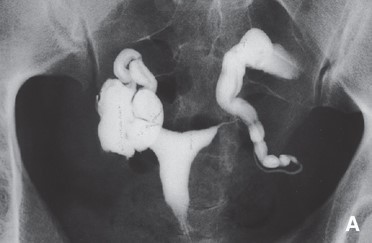

La patiente réalise également cet examen

Question 5. Quelles sont les affirmations vraies ?

On voit deux hydrosalpinx (v. fléchage sur la figure 4)

Il s’agit d’une hystérosalpingoGRAPHIE = radio

L’hydrosalpinx peut entraîner des écoulements dans la cavité utérine et entretenir une inflammation qui est délétère pour l’implantation d’un embryon. L’hydrosalpinx peut également empêcher la rencontre ovule-spermatozoïde dans l’ampoule tubaire

La cavité utérine semble bien opacifiée sans image de défect